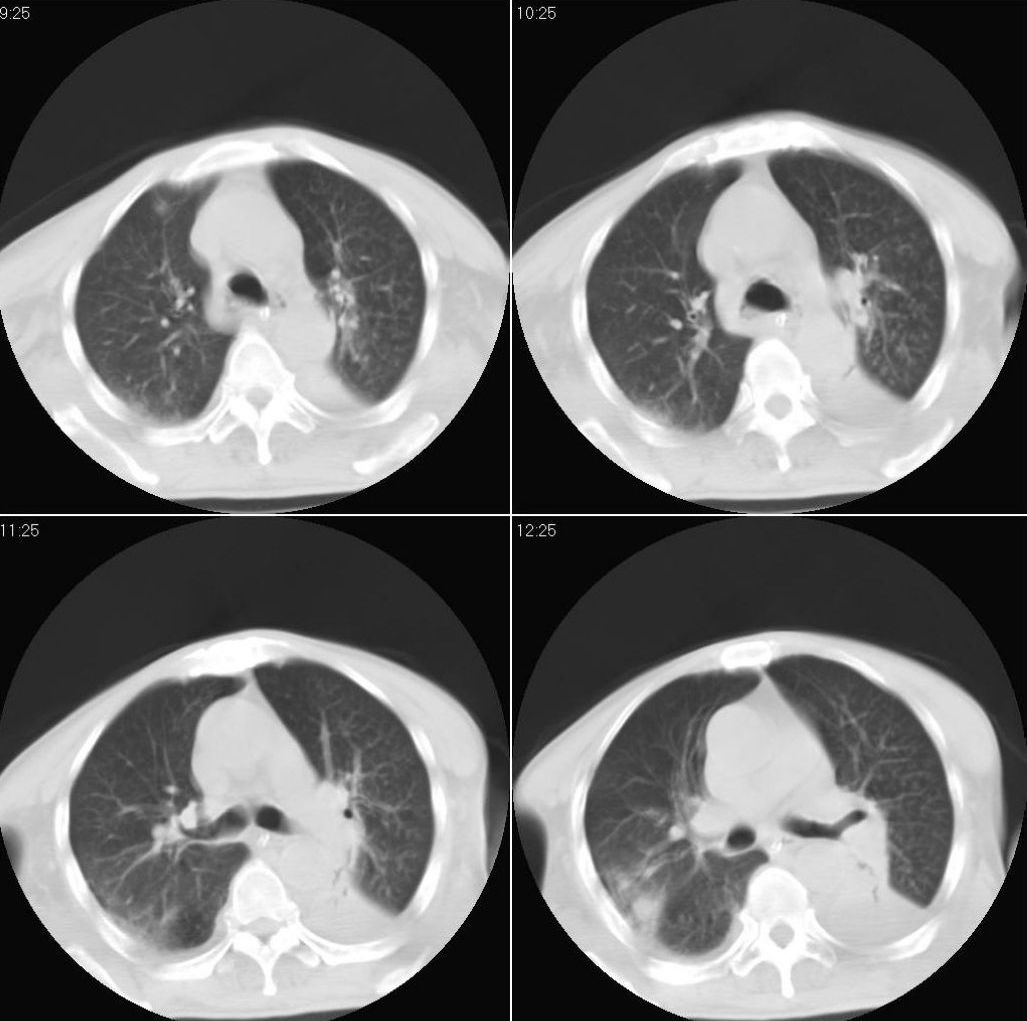

男性,65岁。因外伤来诊。该患者因脑外伤住院。以下是今天的dr和ct:

一周前胸片无异常,不考虑肿瘤,现x片及ct表现应与外伤有关,考虑左侧外伤性膈疝,并左下肺不张。右肺挫裂伤。少量胸水。

一周前胸片无异常,不考虑肿瘤,现x片及ct表现应与外伤有关,考虑左侧外伤性膈疝,并左下肺不张。右肺挫裂伤。少量胸水。支持

1 外伤性左侧膈疝、胸腔积液致左肺下叶不张 2右肺挫伤

右侧第7肋骨腋段骨折并右肺挫伤;左侧膈疝并肺不张。

左侧膈疝并左下肺膨胀不全,,【左下支气管腔变狭窄随诊除外堵塞病变】右肺散在炎症。

右侧肋骨骨折,右肺挫伤,左下肺不张(一周前检查没有,有没有外伤性支气管血块阻塞可能?建议纤支镜检查),左侧外伤性膈疝。